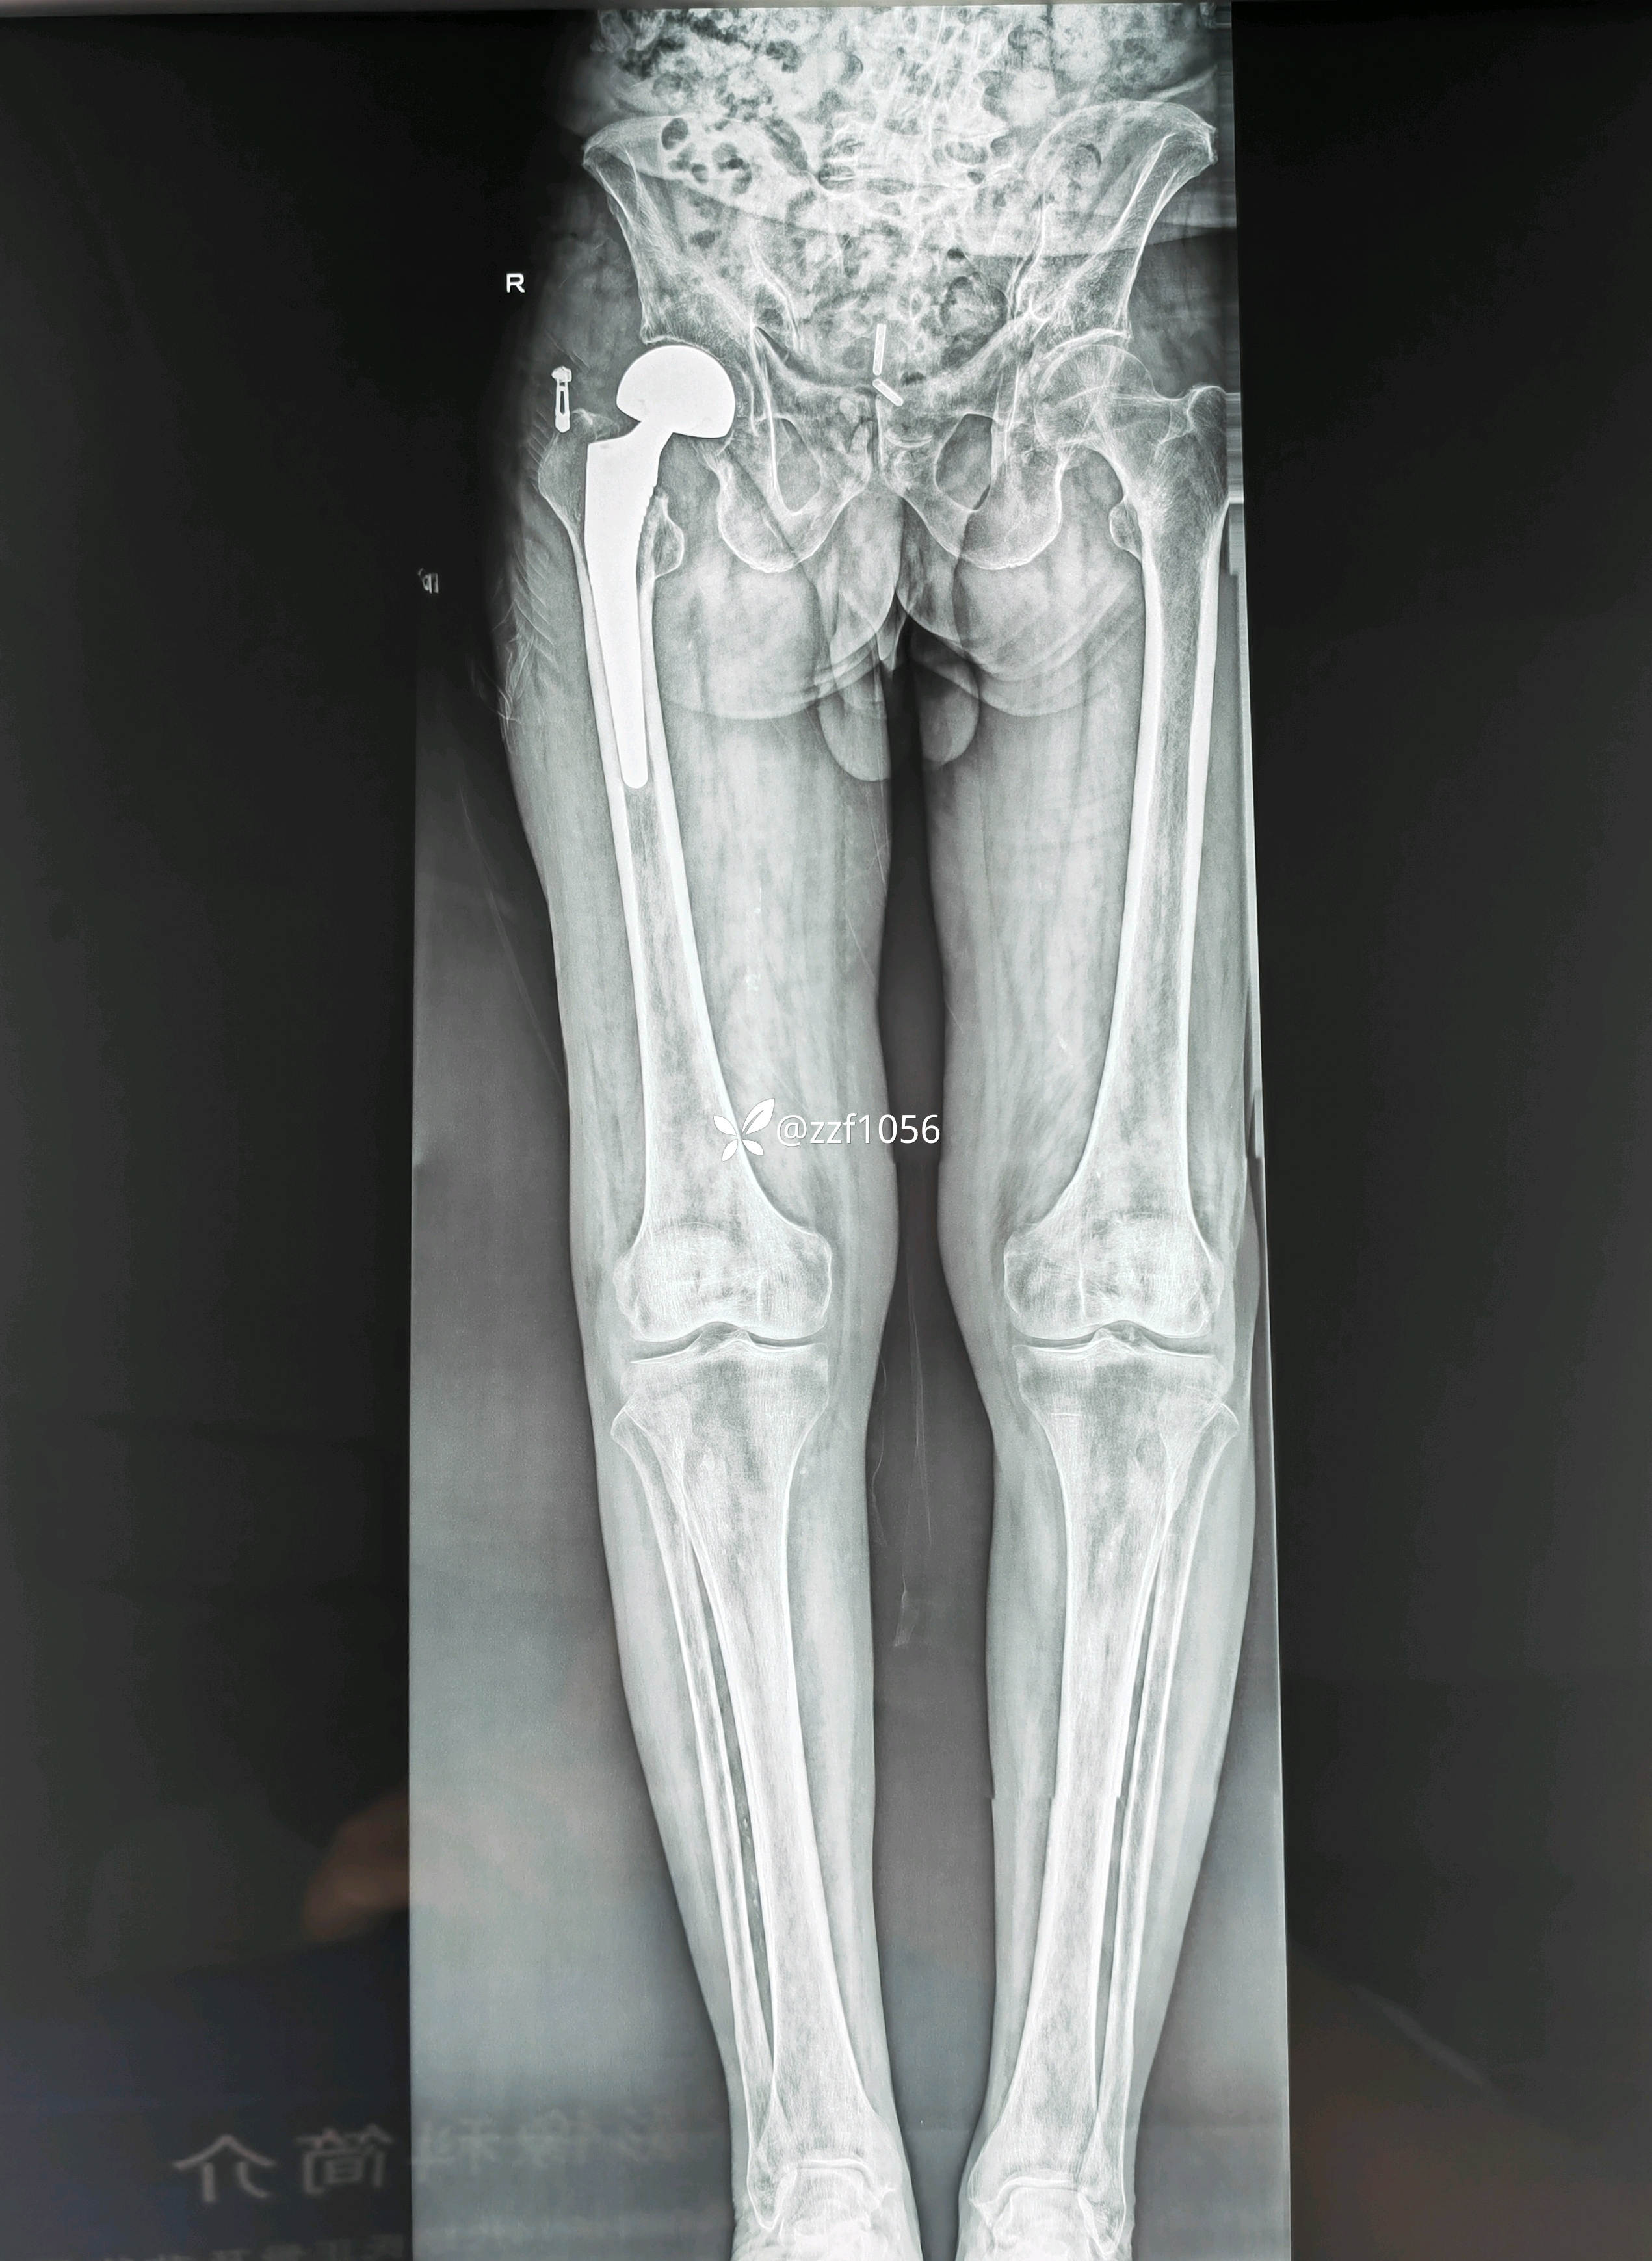

患者男80岁,摔伤右髋疼痛5天,入院。

5天前家里摔伤,附近医院摄片显示右侧股骨颈骨折,因身体状况不好回家保守治疗,疼痛无法耐受再次赴当地县医院就诊,评估身体状况后告知手术风险较大,后经熟人介绍转来我院就诊。

入院诊断:右侧股骨颈骨折

顺利实施手术双动头置换